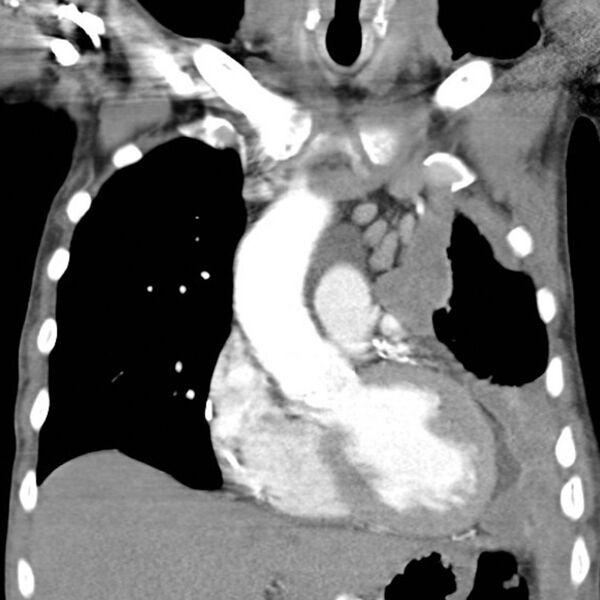

Стирка одежды того, кто работал с асбестом, также увеличивает риск ее развития[12]. К прочим факторам риска относятся генетические факторы и заражение вирусом SV40[3]. Диагноз можно заподозрить на основании результатов рентгенографии грудной клетки и компьютерной томографии. Он подтверждается исследованием жидкости, выделяемой опухолью, либо ее биопсией[2].